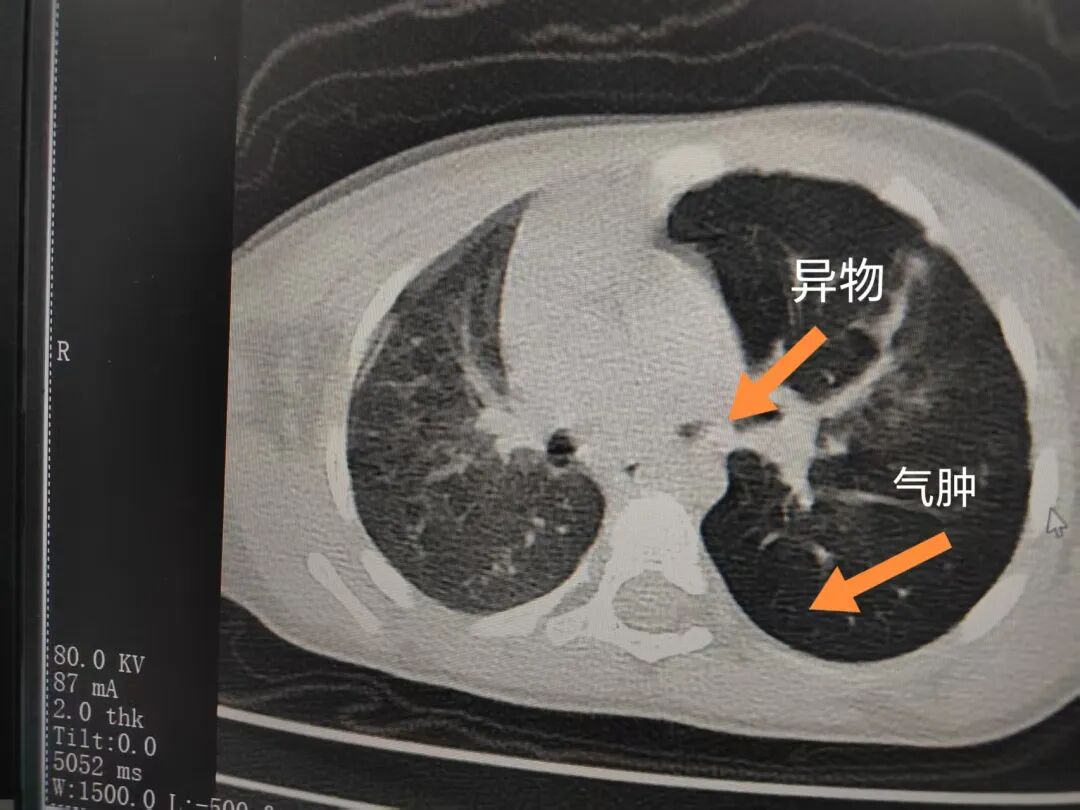

三天后(11月13日),趙寶出現(xiàn)高熱、咳喘加重,家長著急了,再次帶他來到醫(yī)院。CT檢查顯示左肺過度充氣,左肺上下葉支氣管主干見不規(guī)則高密度影,左肺上葉可見大片狀密度增高影,縱隔窗實變,提示為“左側(cè)支氣管內(nèi)異物并繼發(fā)性改變,左肺上葉舌段肺膨脹不全”。

市二院小兒呼吸內(nèi)科團隊迅速為患兒制定了周密的手術(shù)方案,并很快安排了氣管鏡探查。術(shù)中,主治醫(yī)師田慧等憑借嫻熟的氣管鏡操作技術(shù)成功將異物大塊板栗取出。由于板栗在氣管內(nèi)存留時間較長,質(zhì)地軟糯易碎,大大增加了手術(shù)難度。檢查還發(fā)現(xiàn),異物停留部位的氣管黏膜已出現(xiàn)充血紅腫、糜爛,導致患兒住院時間相應延長。此次事件給趙寶的家庭帶來了不小的驚嚇與擔憂,也再次為廣大家長敲響了警鐘。